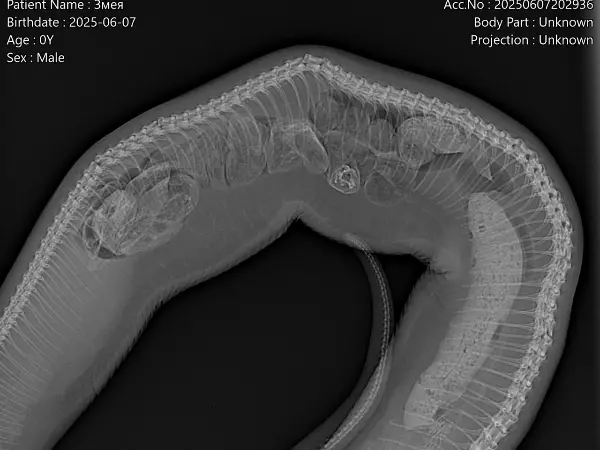

Рептилия долго поджимала наиболее поврежденную часть тела из-за боли. К сожалению, от этого на данном участке деформировался позвоночник. Ветврач говорит, что с этой проблемой справиться уже почти невозможно.